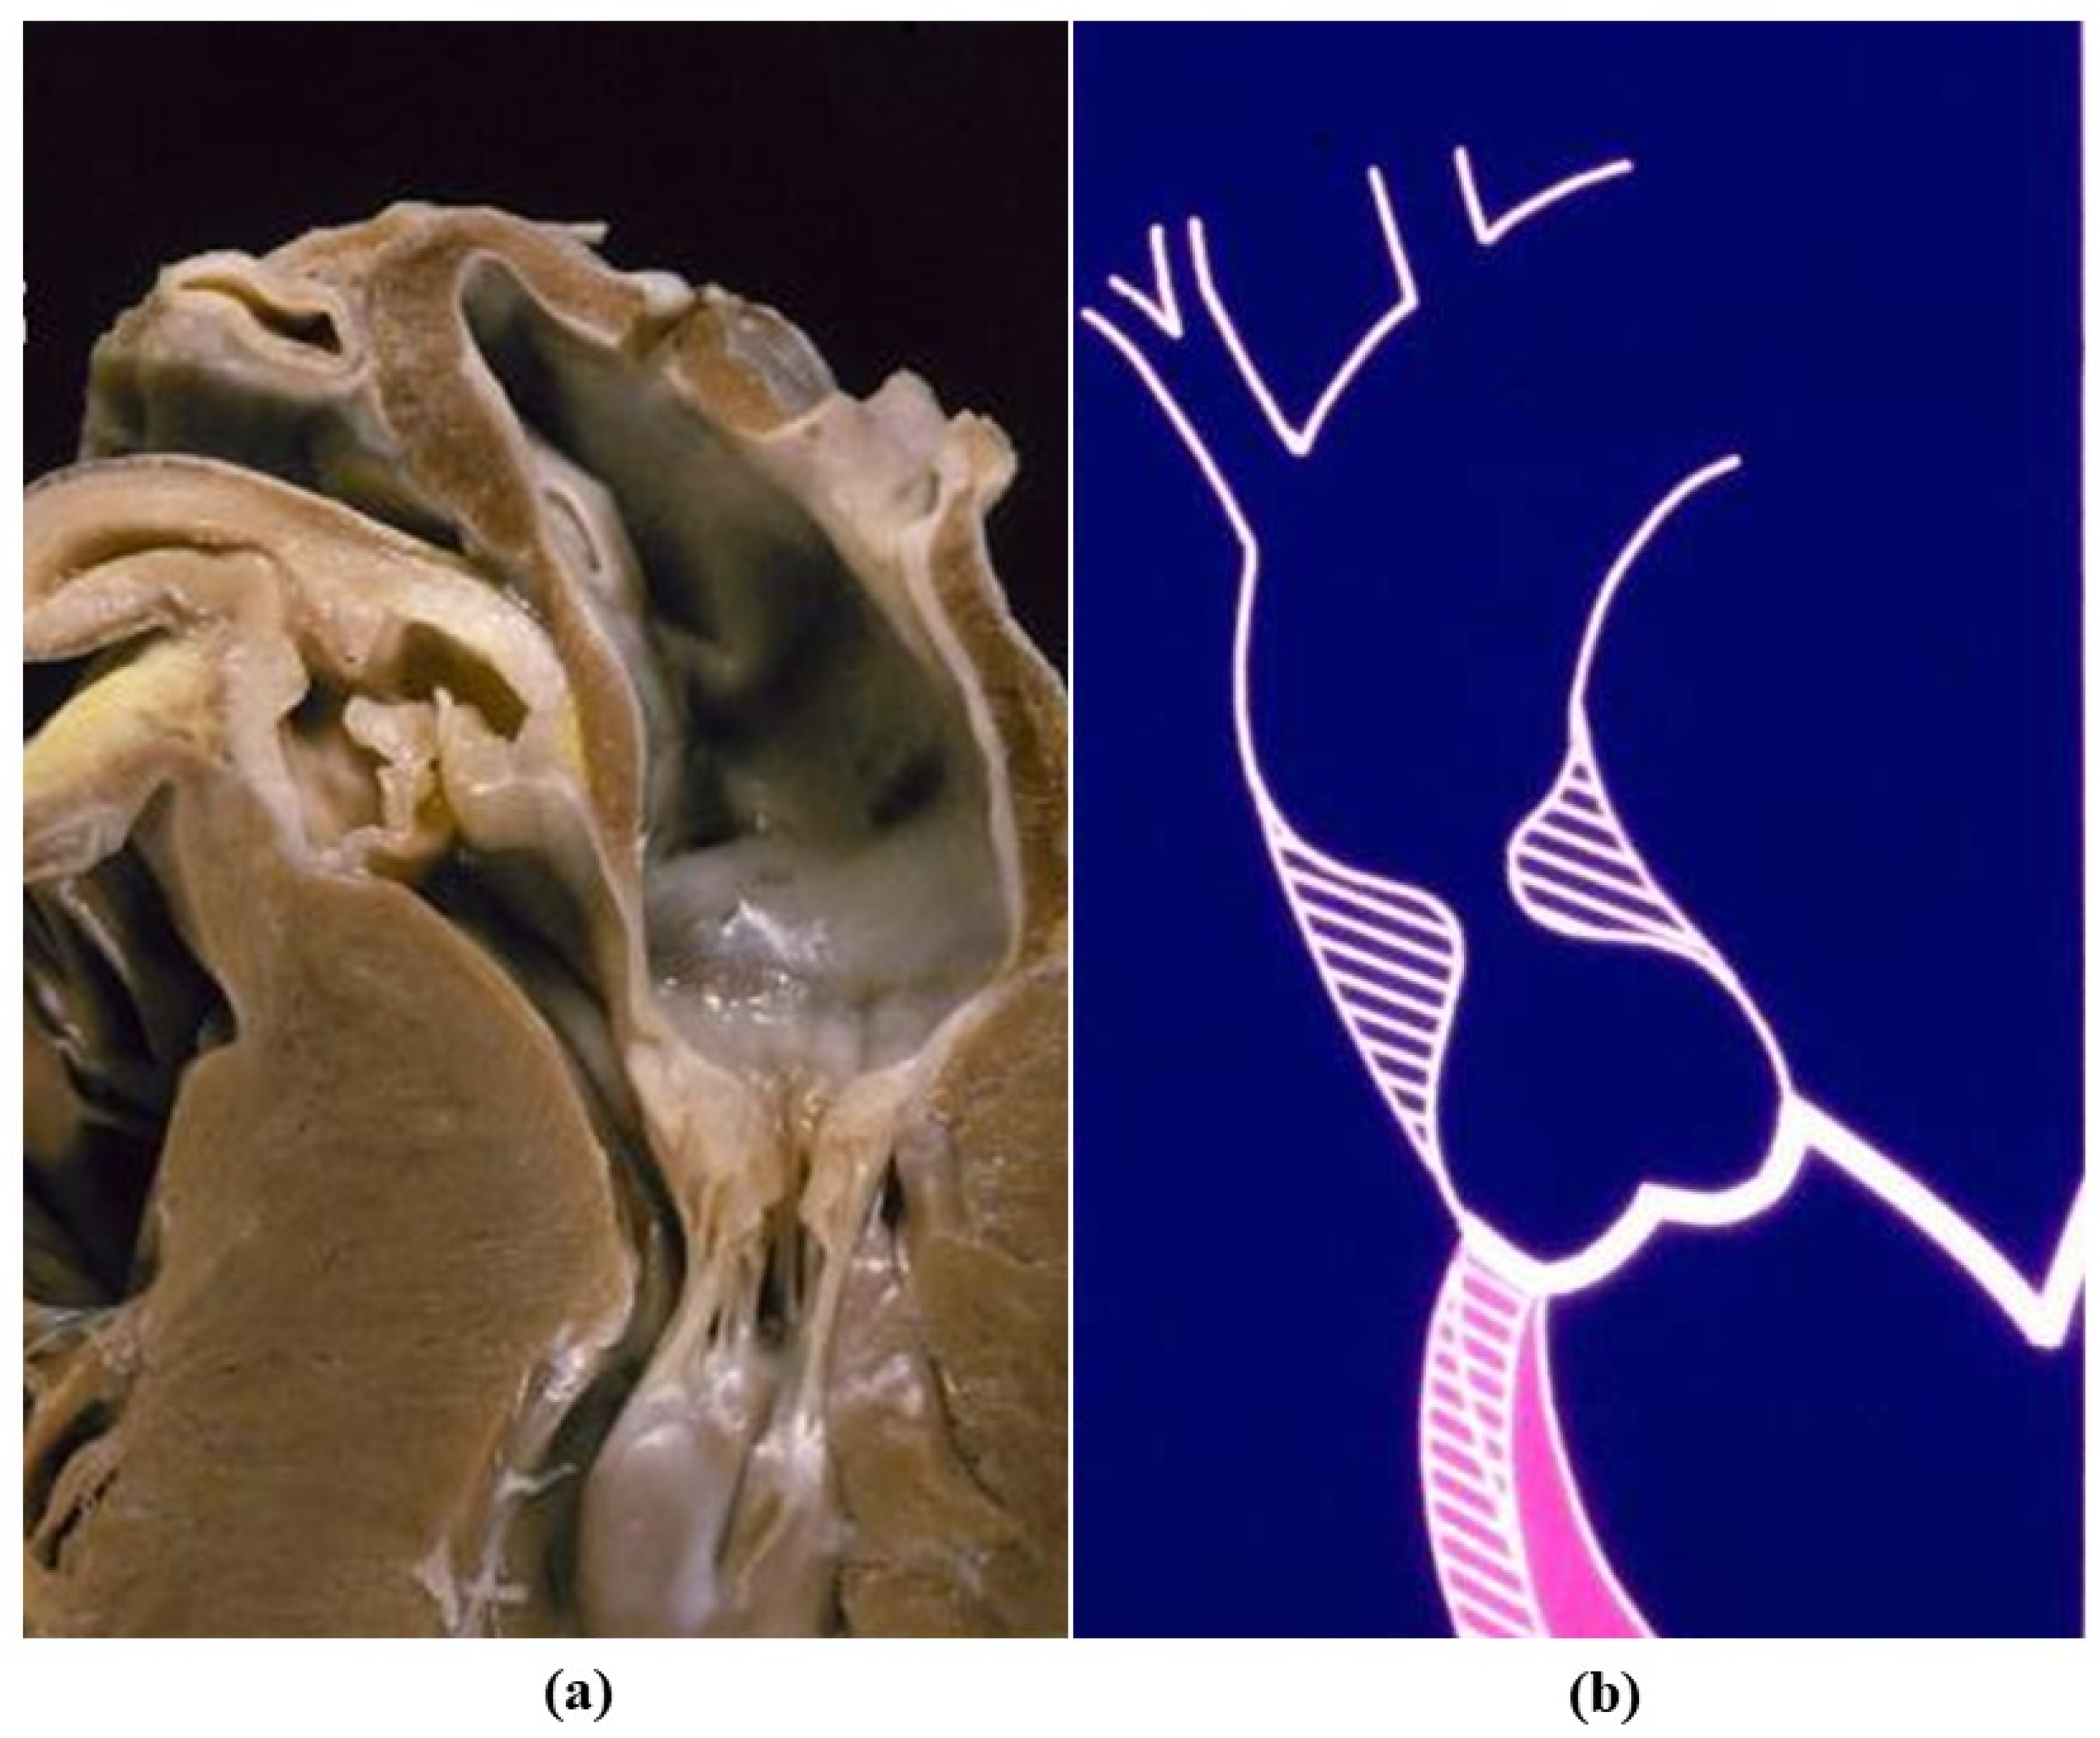

- Cellular repopulation was observed in the outer part of implanted homograft wall by novel smooth muscle cells in the lamellar units (Figure 32a,b) and in the intima with a novel myointimal layer; this layer was noticed also in small animals such as rodents [68]. Novel endothelial cells appeared to line both the aortic wall intima and inflow/outflow at the cusp surface, as well as vasa vasorum, and valve spongiosa appeared repopulated by interstitial cells (Figure 32c,d);

- The origin of repopulated cells may be vasa vasorum for the homograft outer wall and the blood stream itself for cusps. Recently it has been demonstrated in a GFP rodent model that all novel cells belong to the recipient [68]. Bone marrow may be a source of progenitor cells (endothelial and mesenchymal cells) contributing to recruitment of smooth muscle-like cells [69,70]. Circulating bone-marrow-derived endogenous cells can be recruited in vivo by adhering to the intimal surface [71,72] and then recruited, undergoing an endothelial-to-mesenchymal transition (EMT) within the valve, followed by differentiation into interstitial cells that ultimately synthesize and remodel the ECM;